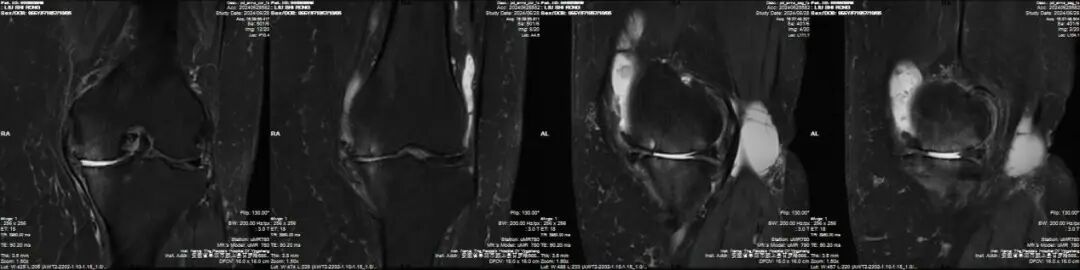

郑奶奶伴有高血压、脑梗死、高尿酸血症等疾病和严重肥胖的特殊体质,术前联系心血管内科、神经内科、麻醉科及手术室等多学科进行会诊,而后经科室全体讨论,结合膝关节磁共振检查,认为郑奶奶是膝关节内侧单间室病变,外侧间室及髌股关节正常,膝关节韧带完整,关节活动范围基本正常,随行左侧膝关节内侧单髁置换术(UKA)治疗。